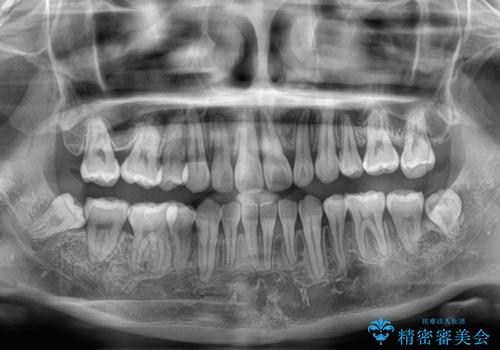

欠損や残存乳歯、深い咬み合わせ ワイヤー矯正で咬合改善

- 後続永久歯の欠損によるスペースと残存乳歯、深い咬み合わせを気にして来院された患者様です。

乳歯を残し、欠損部位のスペースを適正な幅に拡大し、インプラント補綴治療により歯列を整える治療も考えられましたが、ご本人から飛び出している前歯をどうしても引っ込めたいとの要望があったため、残存乳歯ならびに上顎左右第二小臼歯を抜歯して、歯列を整えることとしました。

上下臼歯の咬み合わせ改善には補助装置を、深い咬み合わせ改善にはユーティリティーアーチを活用し、ワイヤー装置にて矯正治療を行うこととしました。

甚大な咬合力に抵抗して過蓋咬合を改善する必要があり、更には口元が引っ込みすぎることがないように仕上げていく必要もあったため、治療期間は3年を超えましたが、当初計画通りの仕上がりで治療を終えることができました。